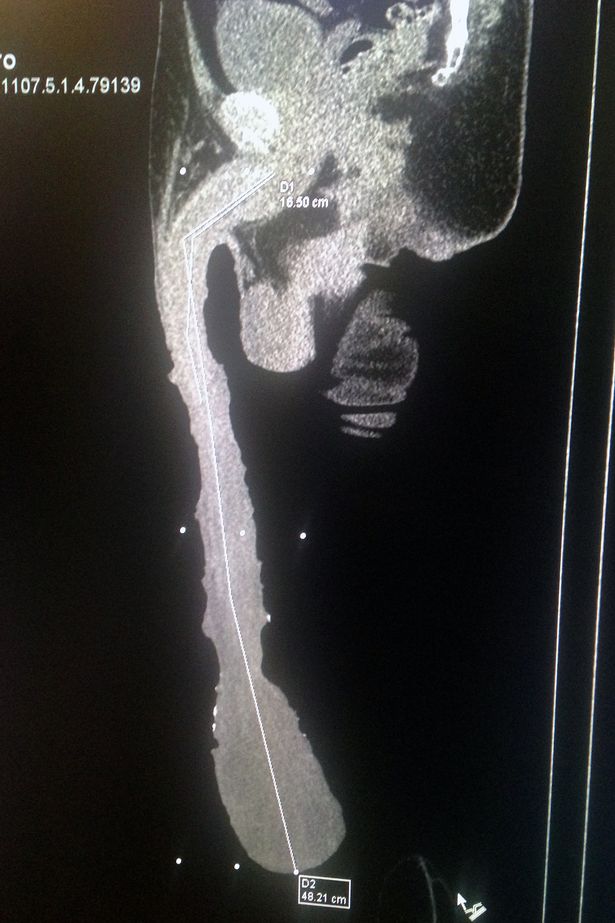

O 54χρονος Μεξικάνος Roberto Esquivel Cabrera είναι ο άνδρας με το μεγαλύτερο καταγεγραμμένο μόριο στον κόσμο.

Το μόριο του ξεπερνάει τα 50 εκατοστά και το μεγαλύτερο του παράπονο, όπως δηλώνει, είναι πως δεν μπορεί να μπει στο Βιβλίο Γκίνες καθώς το «ρεκόρ» του δεν αναγνωρίζεται από την αρμόδια επιτροπή.